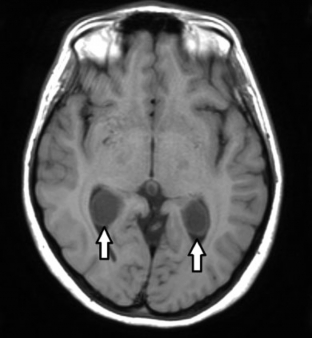

RM de cerebro, cortes axiales ponderados en T1. Se visualiza en los atrios ventriculares (flechas) imágenes quísticas redondeadas, que expanden los plexos coroideos. Las mismas son compatibles con xantogranulomas de plexos coroideos.